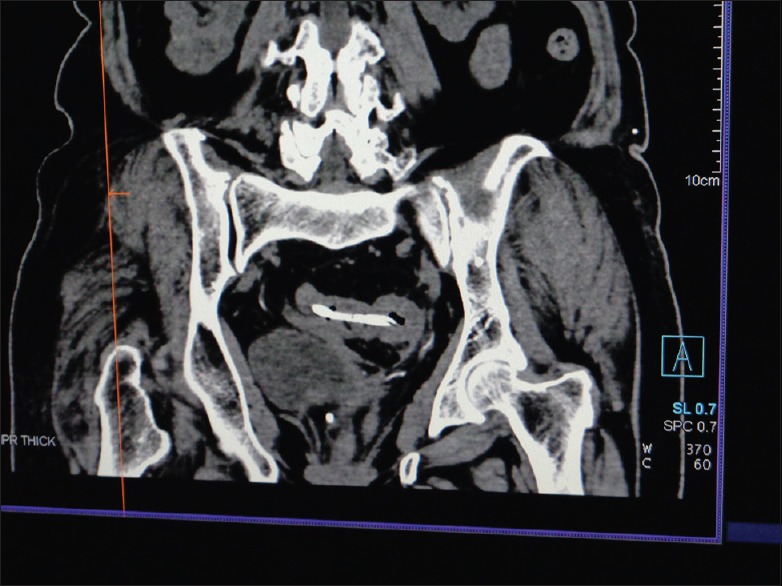

The common bile duct stenting has been a common endoscopic procedure practiced worldwide for the treatment of benign or malignant bile duct obstruction. Although the procedure has shown a very low morbidity, it is not free from complications. Stent migration has been a common late complication seen in 10% of cases presenting with various manifestations depending on the site of impaction. Here, we present a rare case of distal stent migration with impaction in the sacral foramina due to perforation through sigmoid diverticula with review of literature.